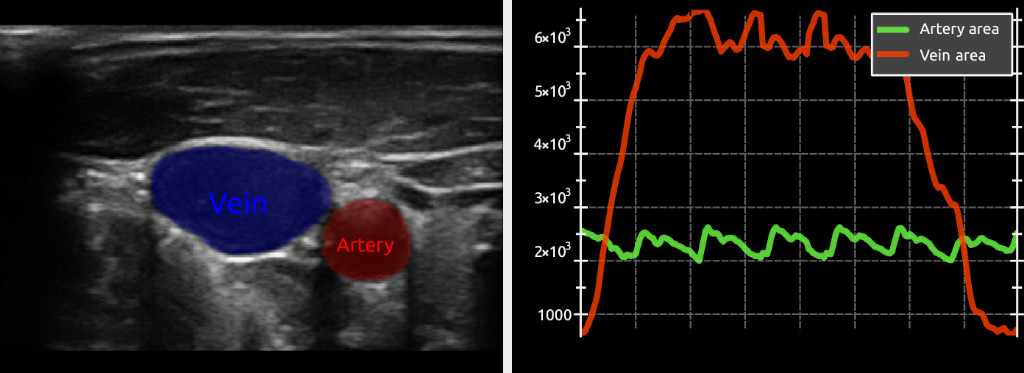

FAST is an open-source framework developed by researchers at the Norwegian University of Science and Technology (NTNU) and SINTEF. The main goal of FAST is to make it easier to do high-performance processing, neural network inference, and visualization of medical images utilizing multi-core CPUs and GPUs. To achieve this, FAST use modern C++, OpenCL and OpenGL, and neural network inference libraries such as TensorRT, OpenVINO, TensorFlow and ONNX Runtime.

• Deep learning – FAST provides a common interface for neural networks supporting different model formats (ONNX, protobuf, SavedModel, OpenVINO, UFF) and backends (Google TensorFlow, NVIDIA TensorRT, Intel OpenVINO, Microsoft ONNX Runtime), making it possible to create real-time neural network pipelines.

• Fast concurrent visualization – Rendering and computation are done in separate threads to ensure smooth responsive visualizations. Several types of visualizations are supported both 3D (mesh, point, line, image slice and volume rendering) and 2D (2D image, image slice and segmentation/label rendering, whole slide image (WSI) pyramids).